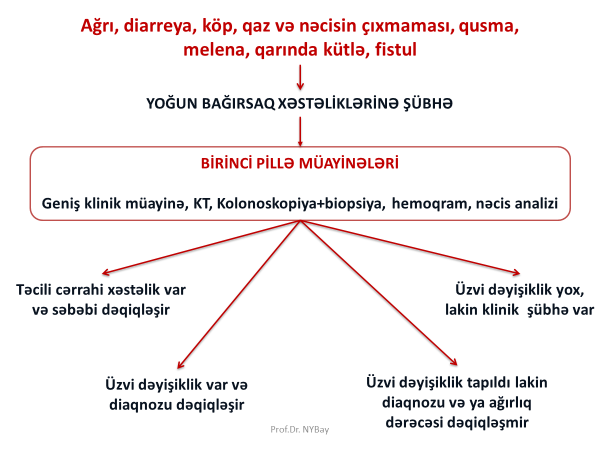

Crohn xəstəliyinin diaqnozu üçün hansı müayinələr vacibdir?

Kolonoskopiya və biopsiya ilə, KT, nəcis analizi

Xoralı kolitin diaqnozu üçün hansı müayinələr vacibdir?

Kolonoskopiya, biopsiya, nəcis analizi

Terminal ileitdə biopsiyanı necə almaq olar?

Kolonoskopla distal ileuma keçərək.